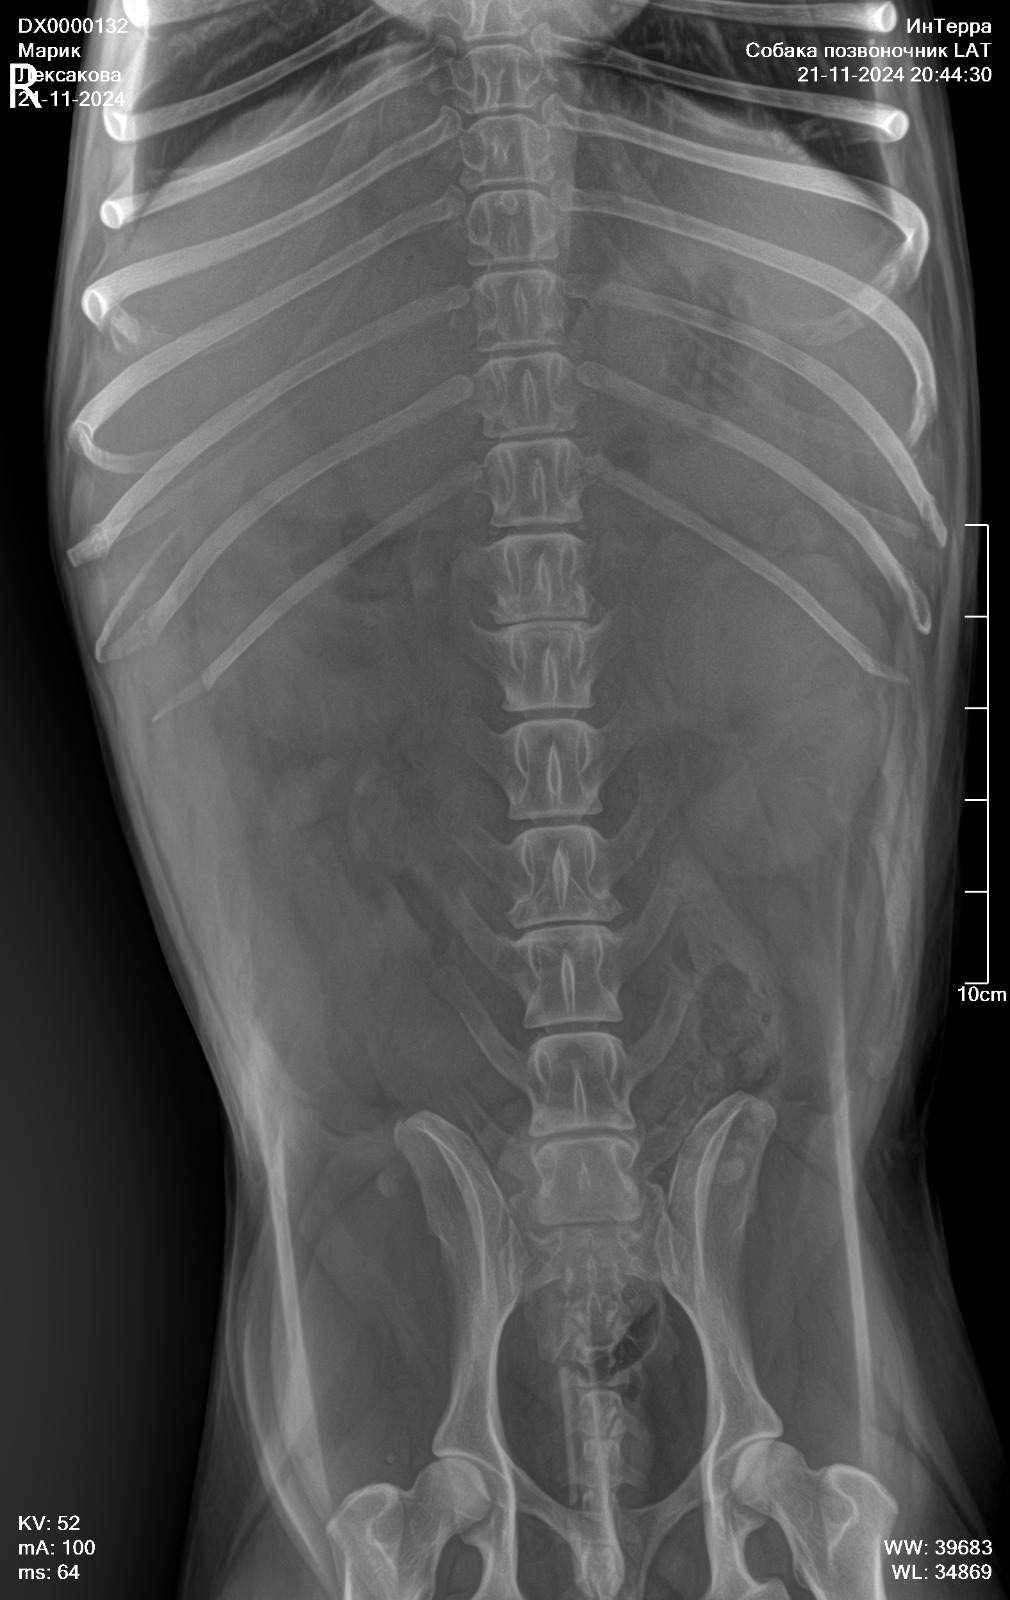

Re: Новосибирск. Цвергшнауцер Марик

Сообщение friedlein »

Рентген позвоночника

Вложения

IMG-20241121-WA0054.jpg

IMG-20241121-WA0047.jpg

IMG-20241121-WA0045.jpg

IMG-20241121-WA0034.jpg

IMG-20241121-WA0041.jpg